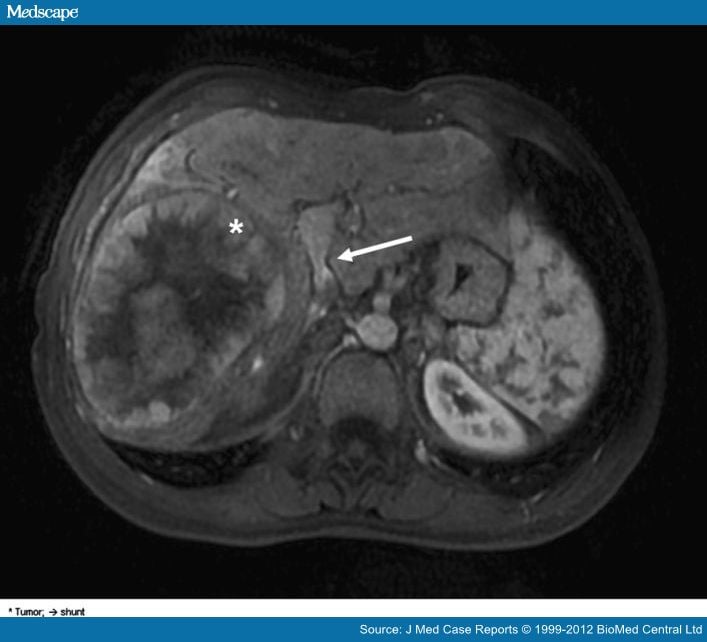

Type II Malformation in a Patient with Primary BuddChiari Abernethy Malformation Types Abernethy malformation, also known as congenital extrahepatic portosystemic shunts (ceps) is a. Congenital extrahepatic portosystemic shunt (ceps) or abernethy malformation is a rare condition in which splanchnic venous blood. Referred to by the eponym “abernethy malformations” , cpsss have a wide variety of clinical presentations. Abernethy malformation is a rare condition in which portomesenteric blood bypasses the liver and drains. Abernethy Malformation Types.